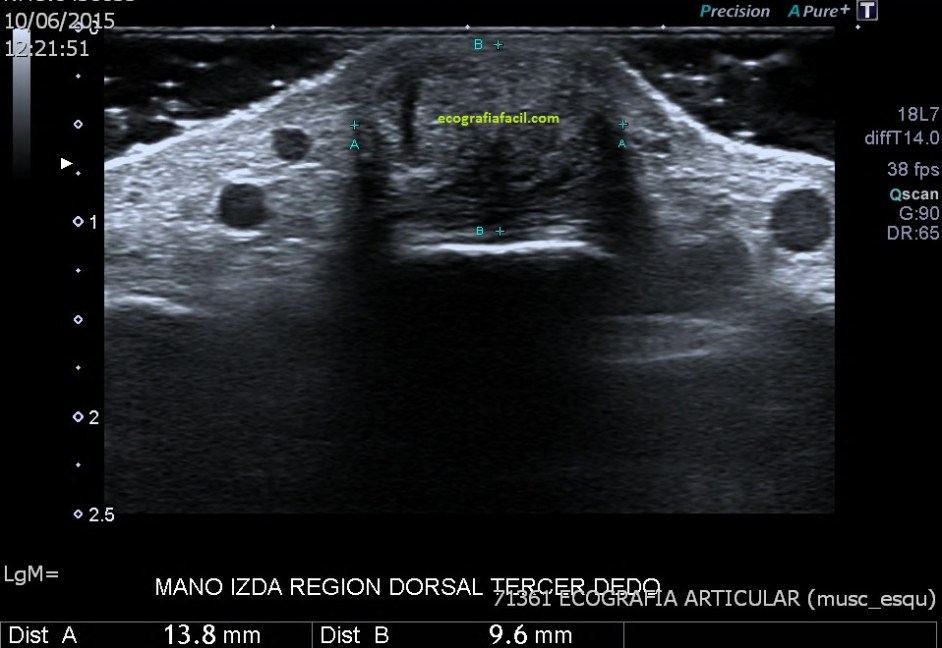

Coincidiendo con el área palpable se identifica una lesión sólida de 13,8 x 9,6 x 17,8 mm, de aspecto heterogéneo, predominantemente hipoecogénica, aunque con áreas más hiperecogénicas en su interior, que predominantemente se encuentra superficial con respecto al tendón extensor del tercer dedo y con discreta vascularización periférica en el estudio Doppler color.

Quiero que te fijes en la imagen 4 y busques y sigas el tendón extensor del dedo, muy fino, observa como se puede seguir su recorrido a lo largo de la lesión producida por el acúmulo gotoso, en la imagen 5 te lo marco con flechas rosas para que te sea más fácil.